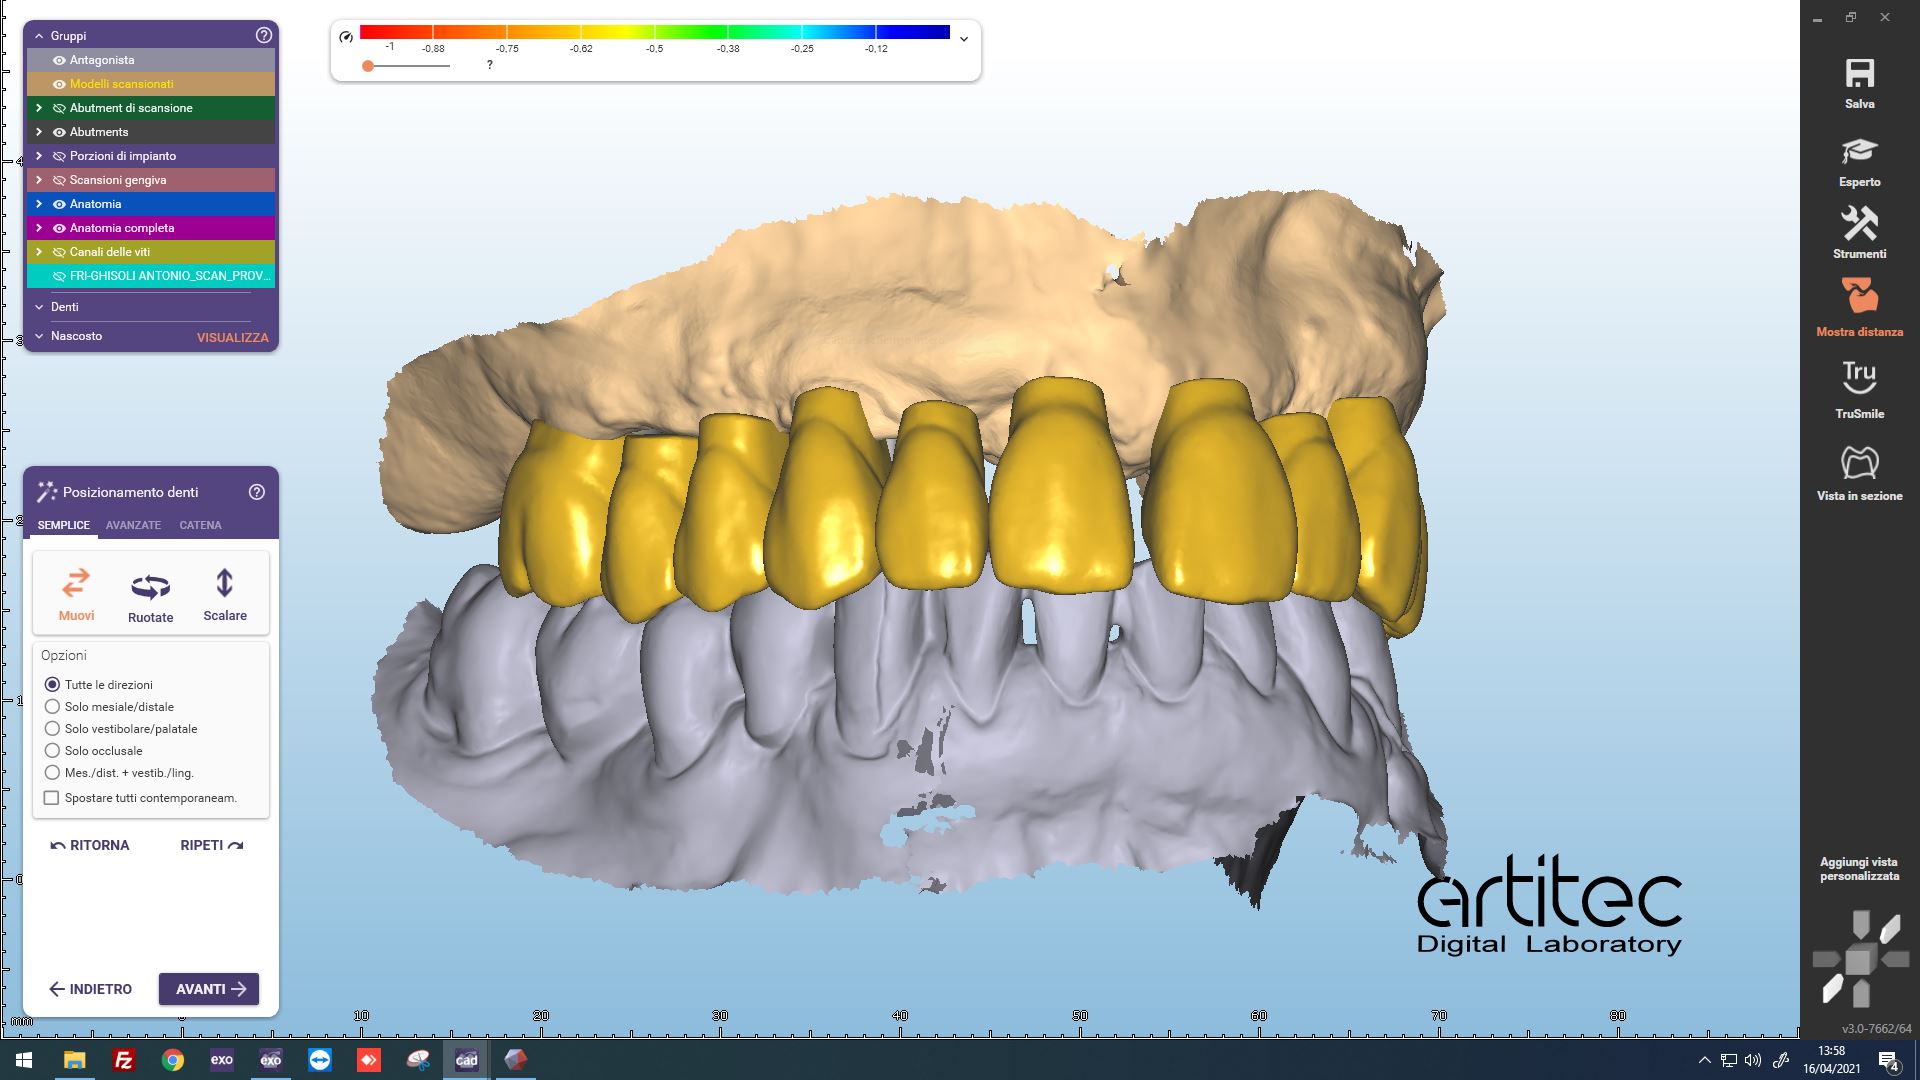

Fig. 6 Posizionamento anatomie CAD/CAM